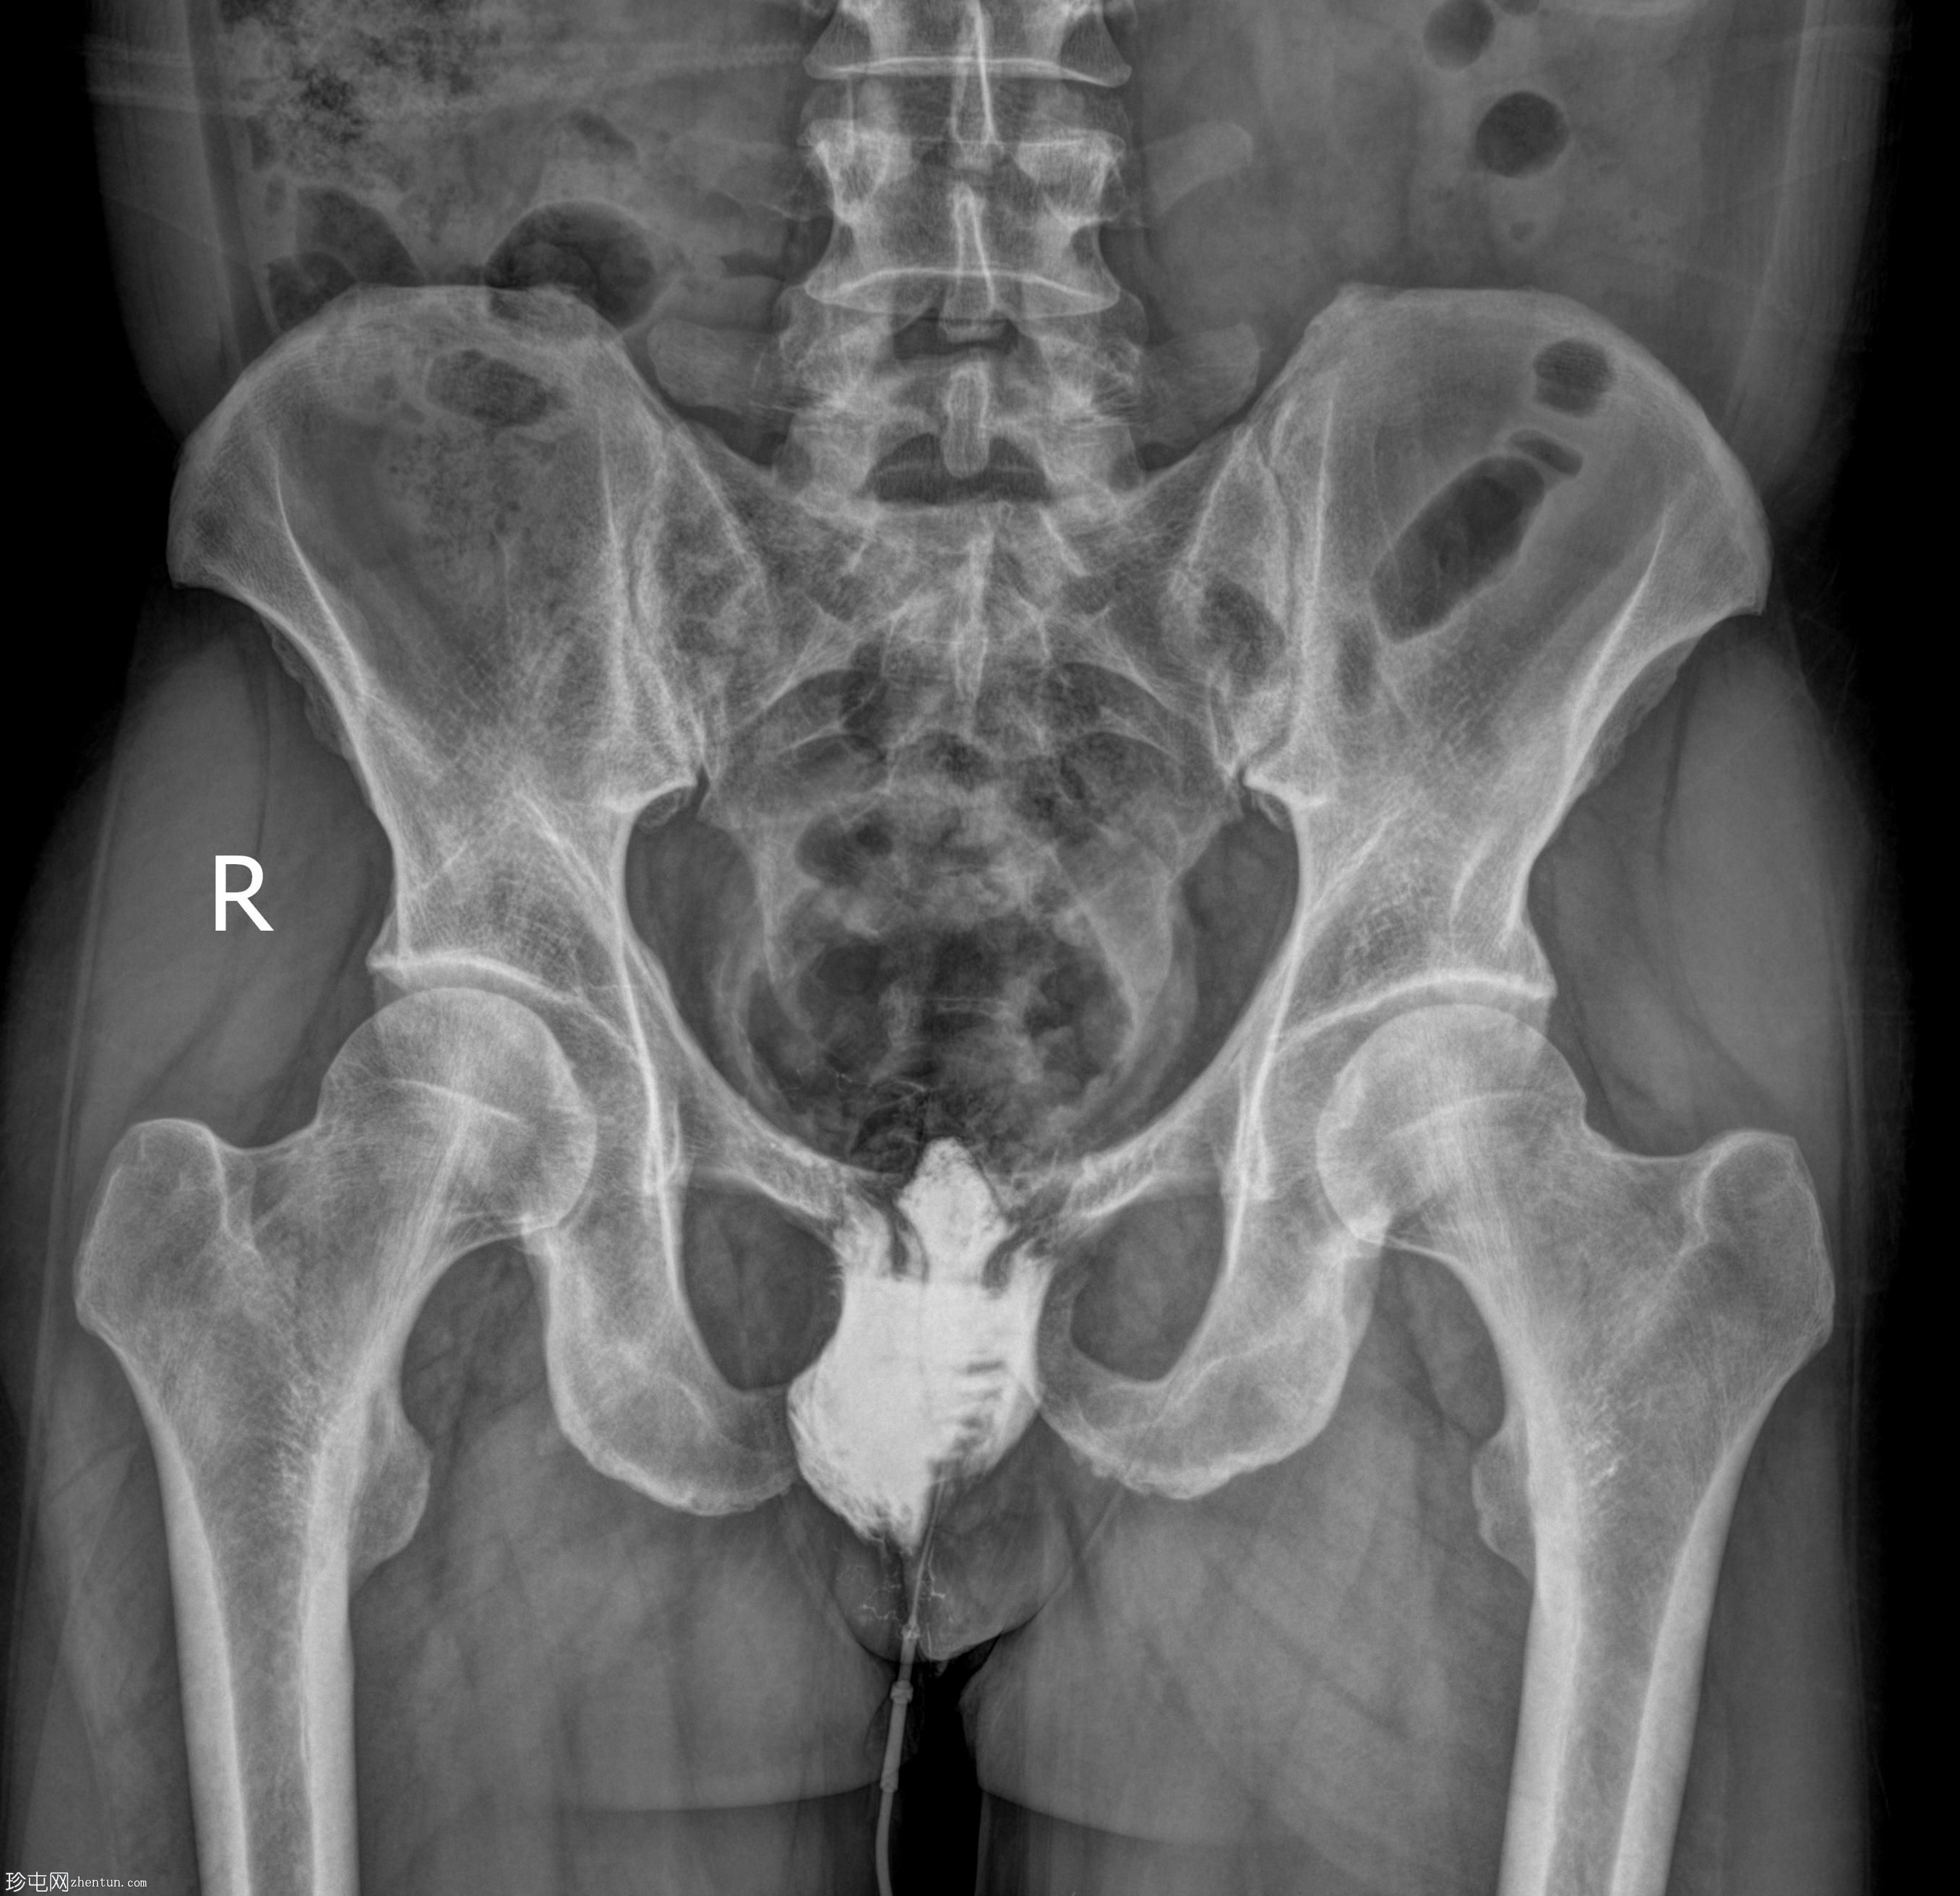

年龄:50岁

性别:男

透视检查

正位

经脓性分泌物开口注入造影剂,显示右侧肛周脓肿显影。

未见造影剂明显外渗至肛管或直肠。

透视瘘管造影图像显示右侧肛周脓肿较大,与肛管或直肠无交通。